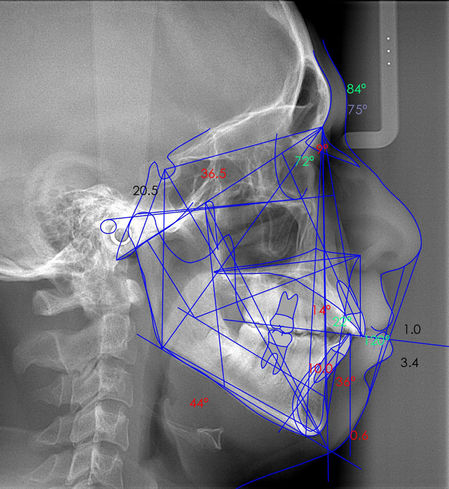

Lateral de Cráneo

Análisis Cefalométrico